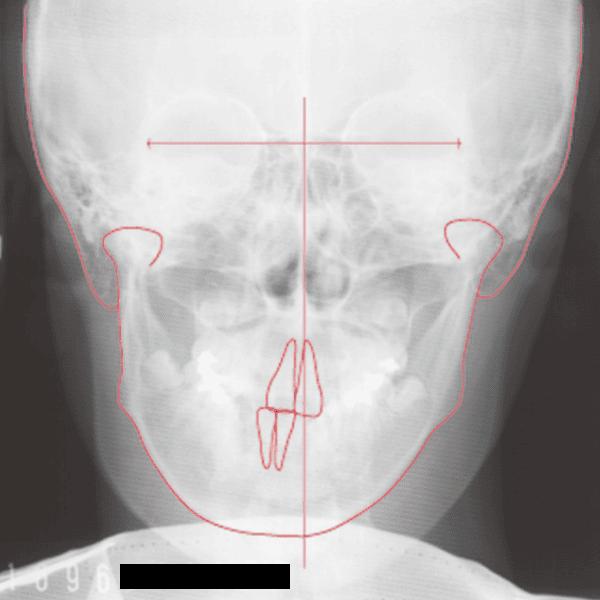

A case of diverted and cross bite during the deciduous dentition. Despite early treatment, the deviation progressively worsened with age, necessitating surgical treatment. At the initial visit, the patient had a deciduous dentition, and observation was planned (3). With the eruption of the permanent incisors, the mandible shifted slightly to the right, resulting in a cross bite (1) At this point, asymmetry can be confirmed in the front view. However, it is slight. The cephalometric X-ray reveals a structure with a slightly dominant mandible, but asymmetry in the mandibular ramus is not observed.

X-rays confirmed significant differences in the length and orientation of the mandibular ramus on the left and right sides. It was determined that orthodontic treatment alone would be insufficient, and a decision was made to proceed with treatment incorporating surgical intervention.